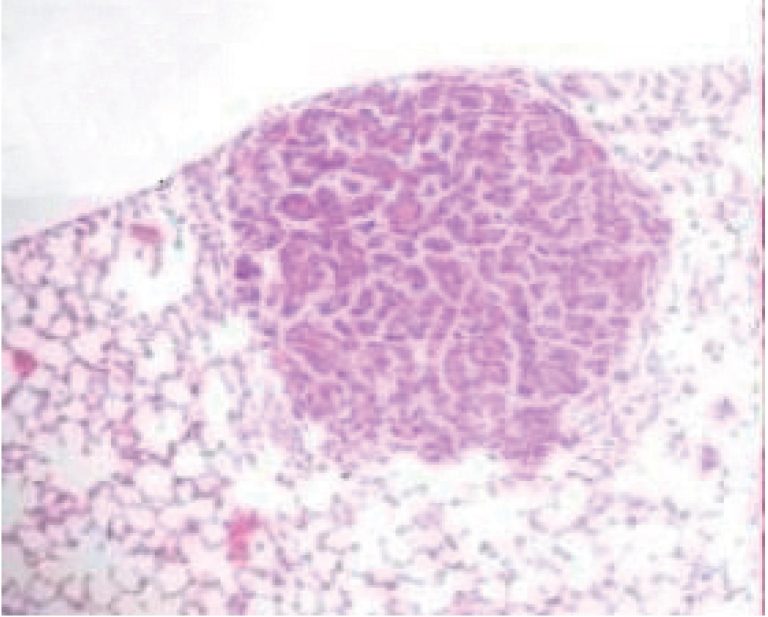

ABSTRACT Objective: To evaluate the effect of janaguba in inhibiting the development of lung cancer in an experimental urethane-induced model. Methods: a total of 3mg/kg urethane was injected in 51 Balb-C mice aged 7-13 weeks of life. Janaguba was administered orally daily in two doses: 0.04 mL (Group 2, G2) and 0.06 mL (Group 3, G3), for 20 weeks. After this period, the mice were sacrificed and the number of lesions counted. Results: The mean weight of Group 2 was […]

Keywords: Lung neoplasms; Mice; Phytotherapy, experimental; Urethane